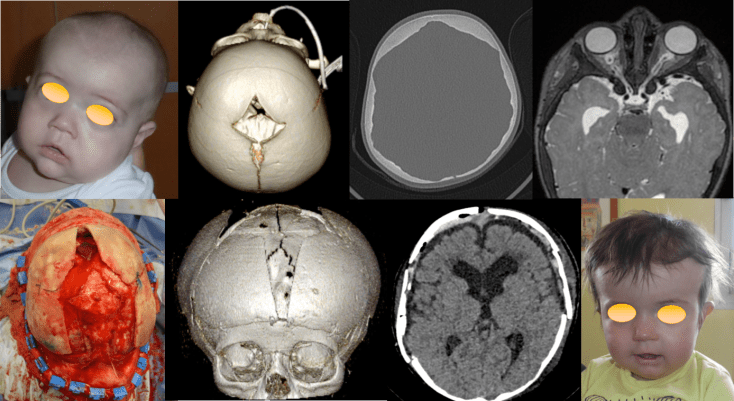

les lacunes crâniennes

on retrouve de façon banale des lacunes pariétales postérieures paramédianes, correspondant aux veines émissaires pariétales.

dans certains cas, ces lacunes sont très étendues, on parle alors de foramina parietalia permagna.

ces lacunes peuvent être associées à une craniosténose syndromique (ci-dessous dans un syndrome de Saethre-Chötzen).